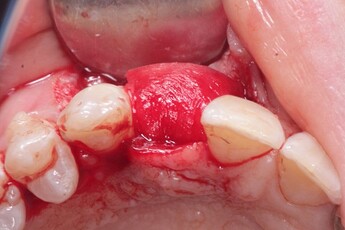

An implant was placed in site #7 with an existing buccal bone defect (Pictures 1 & 2). Prior to placing the bone graft over the implant, the membrane is measured and trimmed and tucked under the palatal flap trying to avoid wetting the entire membrane (Picture 3). The particulate bone graft (DALI Classic Cortical Cancellous Mix) is placed over the implant surface to restore the defect (Picture 4). The membrane is folded over the crest and onto and slightly beyond the particulate bone graft while slowly dropping saline onto the membrane (Picture 5). This enables the membrane to contour and drape over the graft and “seal” the graft off from the surrounding soft tissue (Picture 6 and 7). Sutures are then used to achieve primary closure over the GBR site (Picture 8).

Pic 2

osseoseal-2